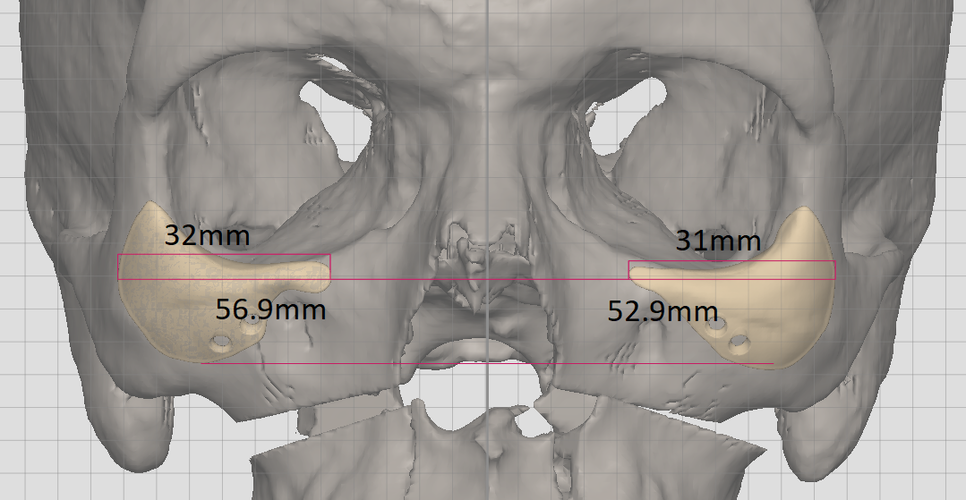

im getting surgery(trimax and infras) soon, any thoughts on this?my left side (the 31 mm) is also less wide in real life, i think would be good to extend it more to the nose area.